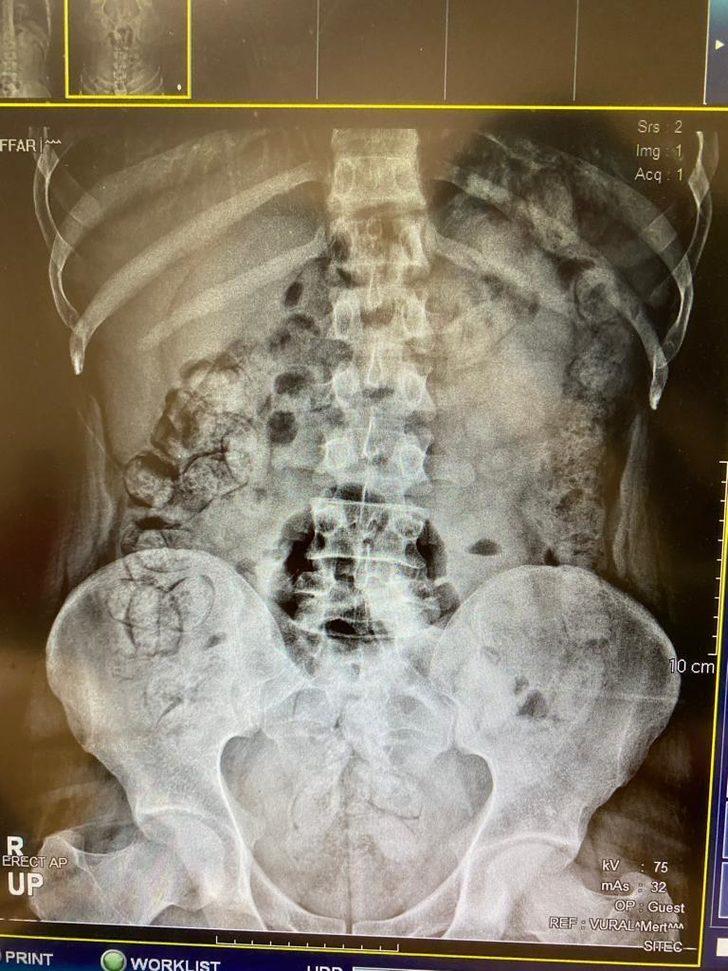

Çekilen röntgen filmlerinde şüphelilerin vücutlarında 62 kapsül eroin ve 210 kapsül afyon sakızı olduğu tespit edildi.

Röntgen çekimlerinde uyuşturucu kapsüllerinin şüphelilerin neredeyse iç organlarının her tarafına yayıldığı belirlendi.

Doktor ve polis, vücutta tek seferde bu kadar yüklü miktarda uyuşturucu görmenin şaşkınlığını yaşadı.

Yapılan kontrollerde ve röntgen çekimlerinde, şüphelilerin vücutlarından 411 kapsül afyon sakızı olduğu belirlendi.

İlk operasyonda ve ikinci operasyonda yakalanan zanlıların, uyuşturucuları bugüne kadar rastlanılmayan "kolonoskopi" yöntemiyle vücutlarına soktukları değerlendirildi.